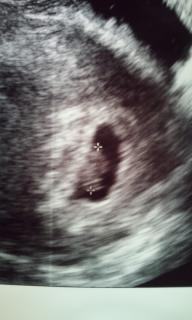

なんとみゆっぺ

第2子が授かりました

ダイヤモンドタトゥーの練習に夢中で生理予定日を5日程忘れてて「胸がはるなぁ~、でもちょっと前凄くお腹痛かったのに…」っと思いつつ念の為検査薬で調べたら陽性反応が

昨日心拍確認して来ました

予定は8月です